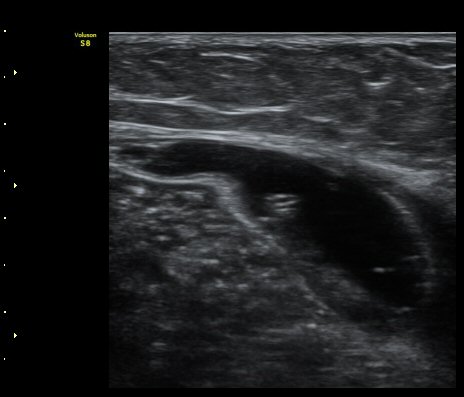

¹«¸ µÚ ¿À±Ý Ⱦ´Ü¸é°Ë»ç¿¡¼ ³»Ãøºñº¹±Ù°ú ¹Ý¸·¾ç±Ù »çÀÌ¿¡ Àú¿¡ÄÚ ¼ö¾×Àú·ù°¡ °üÂûµÈ´Ù(»çÁø 2).